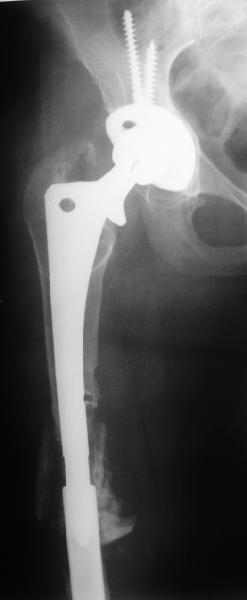

Although, there is just one view, it seems that cement is still holding well on lateral side, cup also seems to be stable, but inside is asymmetric – poly is damaged ... options:

1. "Easy": long lateral plate and anterior strut allograft w/wo bone grafting

2. "Harder" Removal of prosthesis (has to be done if it is loose in remnant of intact proof proximal femur), and new long stem, porous coated prosthesis with new cup (pt is 59years old, probable in good health – survived 6 weeks of traction… this would be my 1st option)

Female, rheumatoid, THA in 2003, car accident in 2006, failed plating. Nailing in Oct 2007. The nail is solid with hollow proximal part where the stem is docked. Last images are in 1 year after

nailing.